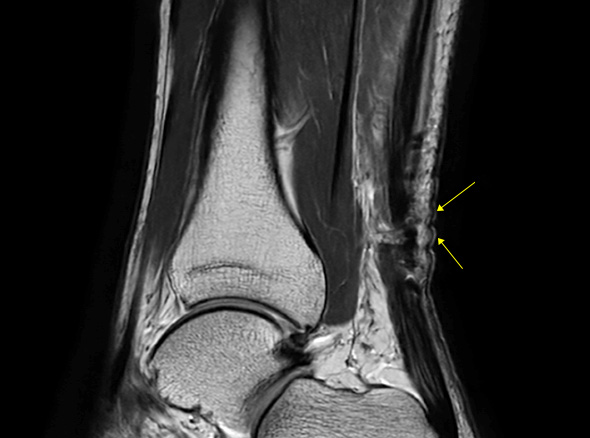

발뒤꿈치 뼈와 종아리 근육을 연결하는 아킬레스건이 부분적으로 또는 완전히 찢어지는 손상입니다.

아킬레스건은 우리 몸에서 가장 크고 강력한 힘줄 중 하나로, 걷기, 뛰기, 점프 등의 동작을 수행하는 데 중요한 역할을 합니다.

* 환자에게 받은 소중한 자료입니다.